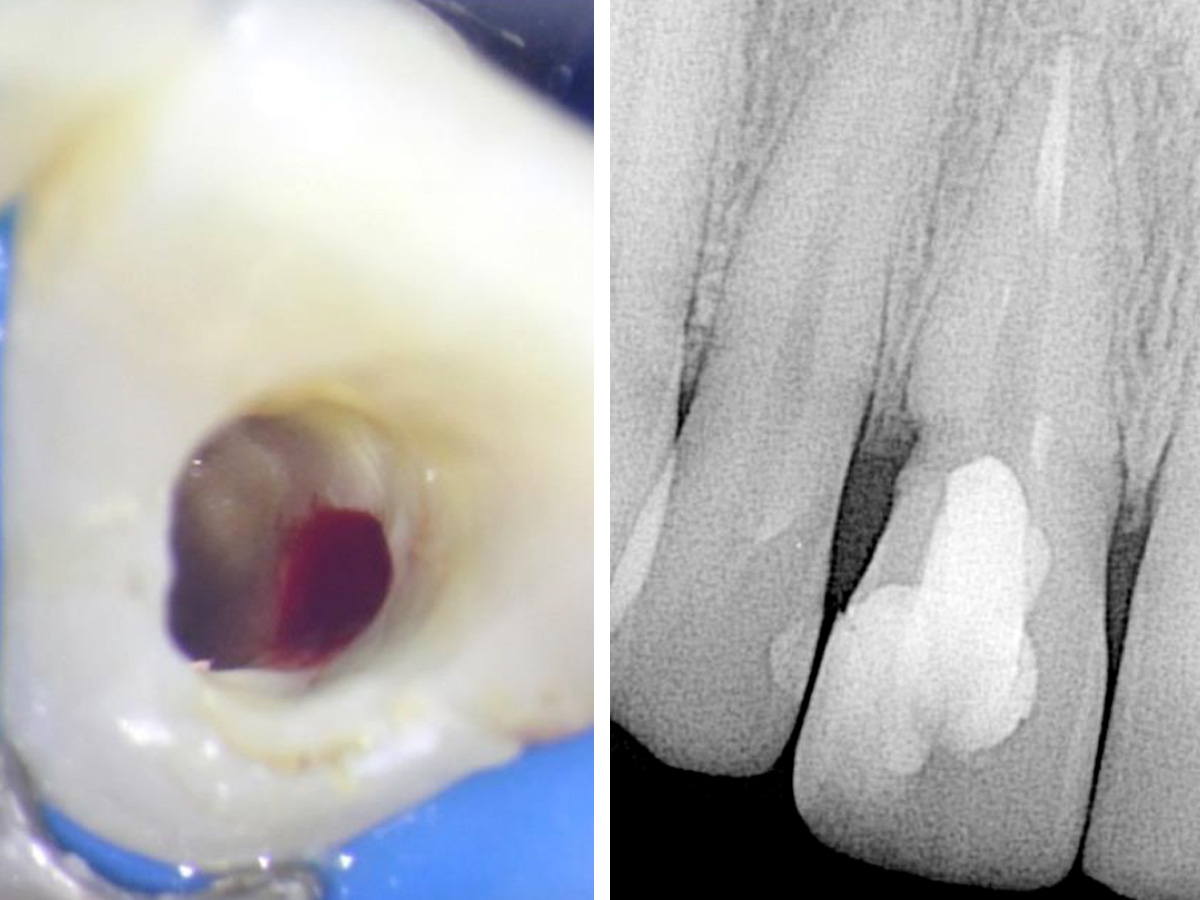

Abbildung 1

Klinische und röntgenografische Ansichten zeigen eine Fistelbildung, die bei genauerer Untersuchung zu einem distal liegenden, zervikalen Defekt an Zahn 11 führte.

Eine 29-jährige kaukasische Frau stellte sich mit Beschwerden an Zahn 11 vor, der wackelte und am Zahnfleisch Eiter aufwies. Ihre medizinische Vorgeschichte war irrelevant. Ihre zahnmedizinische Vorgeschichte beinhaltete eine Wurzelbehandlung, die 11 Jahre zurücklag. Der Zahn hatte sich etwa vier Jahre zuvor verfärbt und wurde mit Wasserstoffperoxid gebleicht. Die klinische und röntgenografische Untersuchung zeigte eine Fistelöffnung, die zu einem resorptiven Defekt im zervikalen Bereich des Zahnes führte (Abb. 1).